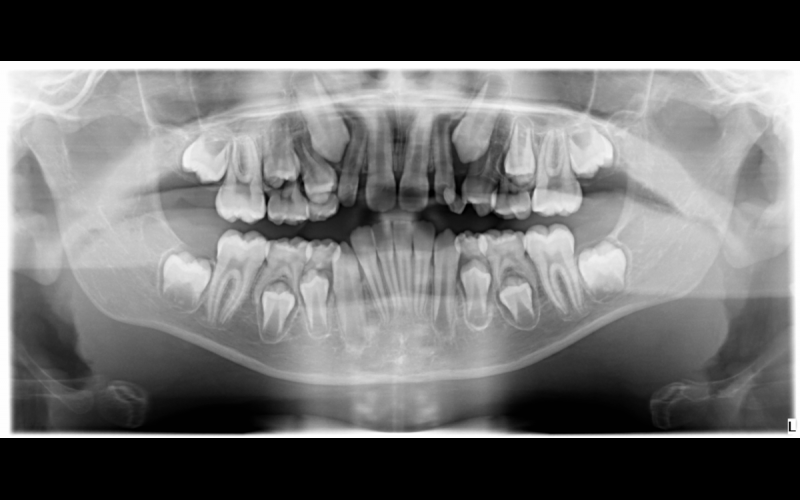

Es muy común ver padres preocupados cuando les indicamos que tenemos que realizar una radiografía a sus hijos, y lo entendemos, pero las radiografías en niños son extremadamente útiles para la detección temprana de enfermedades y ver problemas en el recambio dental como agencias, o dientes supernumerarios.

Contamos con la posibilidad de realizar radiografías pequeñas para uno o dos dientes con una dosis técnicamente inexistente, ortopantomografías que nos dan una información magnifica del estado general de la boca del niño, y en ciertos casos necesitamos realizar un escáner para poder ver con volumen huesos y dientes, pudiendo dar un un diagnostico exacto.

Hay muchas enfermedades de los dientes, como la caries, que no se pueden ver de manera directa, sobre todo cuando están empezando, y por lo tanto una radiografía nos ayuda a revelar cosas como:

• Pequeñas áreas de caries entre dientes o debajo de empastes antiguos.

• Caries profundas.

• Fracturas de dientes o huesos, por traumatismos.

• Enfermedades de la encía, como la periodontitis.

• Abcesos o quistes.

• Anomalías de desarrollo.

• Ausencia de dientes, o exceso de ellos.

• Algunos tipos de tumores.

La frecuencia con la que se deben hacer las radiografías depende del estado actual de la salud bucodental, de la edad, del riesgo de caries que pueden tener el niño, y signos y síntomas que nos hagan intuir alguna enfermedad que pueda estar desarrollando.

Es fundamental ver el recambio dental para adelantarnos a posibles problemas y poder dar una pauta de revisiones acorde al estado de cada uno.